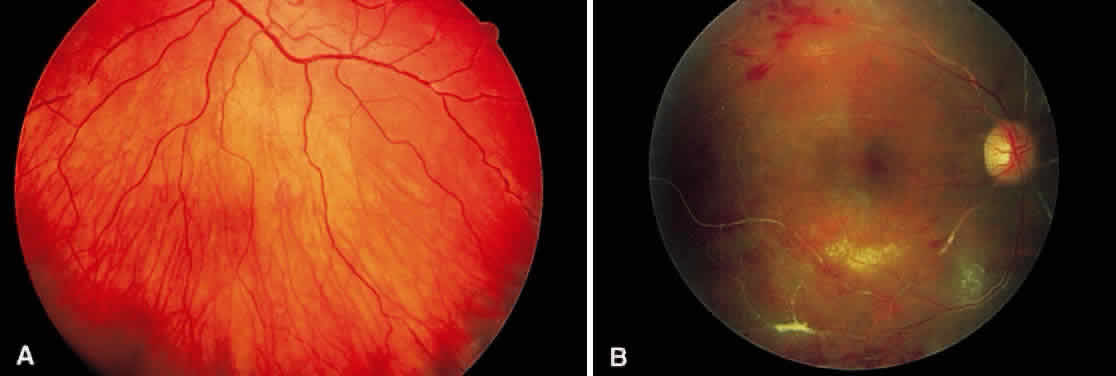

In the century since Henry Eales' observation of altered retinal veins, many investigators have described Eales' disease as a primary disease of altered retinal veins. Elliot and Harris suggest the term periphlebitis retinae for this disorder.4 However, recent reports suggest equal involvement of arteriolar and venular sheathing. Because of the evidence of arteriolar involvement (see Fig. 1B), this disease should be considered as a retinal vasculitis or vasculopathy. Others have used the term primary retinal perivasculitis.8 Cystoid macular edema, vitreal cells, keratic precipitates, and cell and flare in the anterior chamber have been observed in patients with Eales' disease.3